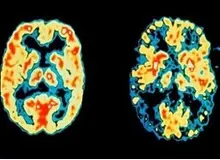

محققان ایتالیایی دریافتند که افراد دو زبانه در آزمونهای حافظه در مقایسه با افرادی که به یکزبان صحبت میکنند بهتر عمل میکنند.